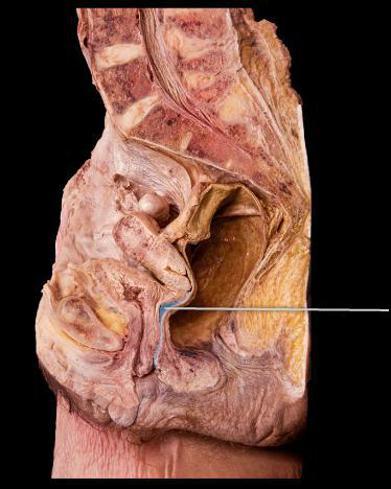

Identify the highlighted layer of the uterine wall

Endometrium

Identify the highlighted uterine layer.

Myometrium

Identify the highlighted tissue in the vaginal wall.

Stratified Squamous Epithelium

Urinary Bladder

Identify the highlighted structure.

Vagina